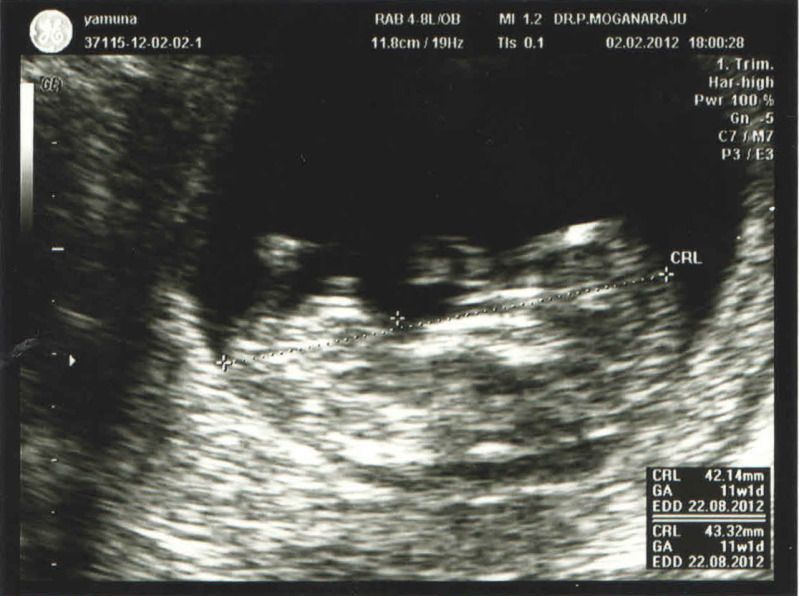

第二次產檢 2/2/2012

醫生幫我量 ...

雪雪 发表于 2-2-2012 07:42 PM

终于产检回来咯。。。我跟你的EDD相差几天而已哦。。。羡慕你可以看到宝宝手舞足蹈的。。。

我那天去看,宝宝好像在睡觉列。。。

你的医生用帮你量颈的厚度哦,我的都没有 |